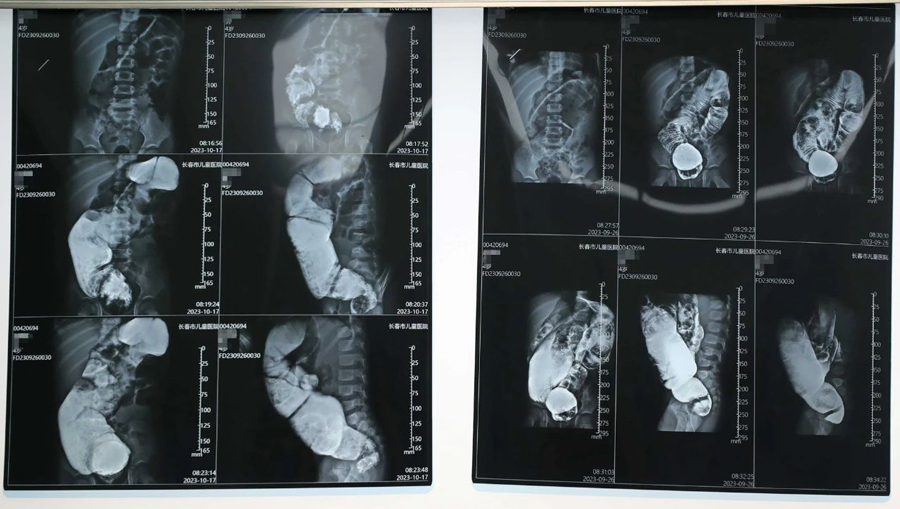

小旭本应在出生后3—6个月手术最佳,但因种种原因,治疗被拖延了。检查中医生发现,小旭为短段型巨结肠,因病程太长,导致肠管梗阻扩张严重、病情复杂,其中,扩张肠管最宽处可达12cm。手术切除缺乏神经节细胞的狭窄肠段及扩张失去正常功能的扩张段肠管,这是目前最有效的治疗方法。医生经过与家长反复沟通,确定了手术治疗方案。

经过充分的术前准备,小旭的肠道具备了手术条件,在完成相关检查和化验后,10月21日,首都医科大学附属北京儿童医院移植科主任、普通外科副主任、医学博士张廷冲,携手蜜桃视频 普外、新生儿外科主任崔钊团队,以及麻醉科、手术室人员,共同组成手术团队,行腹腔镜辅助下巨结肠根治术。张廷冲博士主刀,团队默契配合,先游离盆腔病变肠管,这一操作要求精细、精确解剖,难度很大,一旦损伤输尿管、盆神经和盆底肌肉,容易日后出现大小便失禁。术中取快速病理,使手术切除病变肠管更为精准、可靠。接下来,打开肛门黏膜层,拖出切除肠管,将保留的正常肠管与肛管黏膜吻合。在团队的共同努力下,手术的一系列操作都非常顺利,切除病变肠管约45cm,实现了精准、微创、安全、美观。